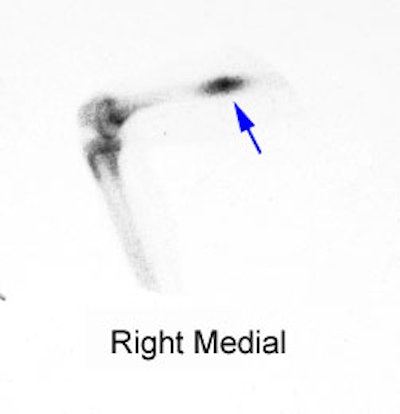

|

Right femoral osteoid osteoma: Flow (click to enlarge) and blood pool images demonstrated a focus of increased activity within the right mid-femoral diaphysis (black arrows). Intense tracer accumulation could be seen in this region on the delayed images. A delayed right medial spot image demonstrated a focal area of even greater activity (blue arrow) within the diffuse abnormality corresponding to the lesions nidus. Plain film (click to enlarge) demonstrates the characteristic appearance of an osteoid osteoma with a dense region of reactive sclerosis surrounding a central area of lucency (white arrow) (click image to enlarge) |